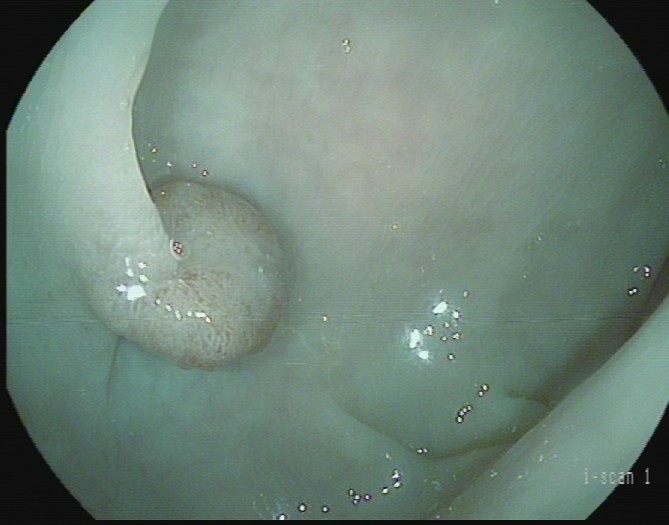

黄先生(32岁,升结肠息肉,图4)

肠镜一照,息肉现形!形态各异的大肠息肉,离癌有多远?(图4)

图4

病理诊断:潴留性息肉(或称幼年性息肉)。

解读:这类息肉常见于儿童和青少年,但成人也可发生。是黏膜腺体扩张、分泌物潴留形成的错构瘤性病变,本质上是良性,通常不具有癌变潜能。距离癌:基本安全,良性息肉。